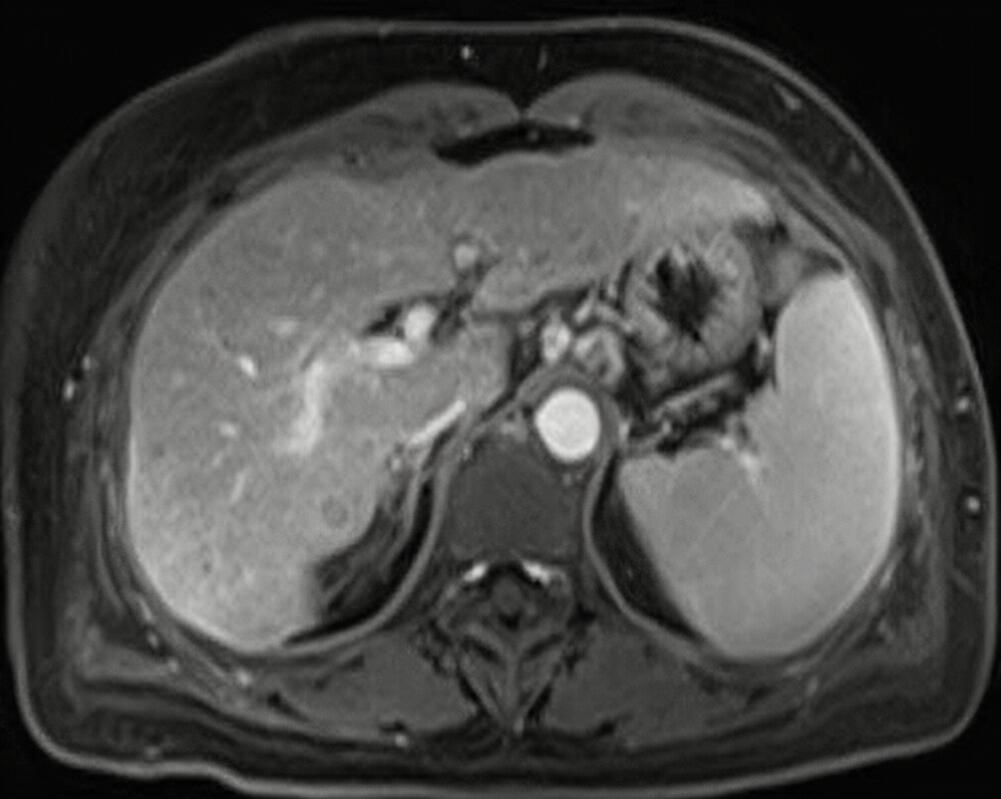

“据了解,该男子去世前两天就开始出现胸闷,夜间有胸痛,但他没有引起重视,后来到当地医院就诊,但由于医疗设备落后无法确切的诊断出其病情。“如果当时及早来大医院检查的话,这一切有可能不会发生。”市人民医院医疗急诊科副主任说:“这位男子他身体肥胖,并有长期吸烟史,每天一包,初步考虑其可能为心肌梗死导致的心源性猝死。“杨医生分析,该男子有多重心血管高危因素,两天前出现胸部不适时没有去医院就诊,说明当时可能有冠状动脉的栓塞情况,却未得到及时明确和处置,后续疾病进一步发展,最终导致了悲剧。